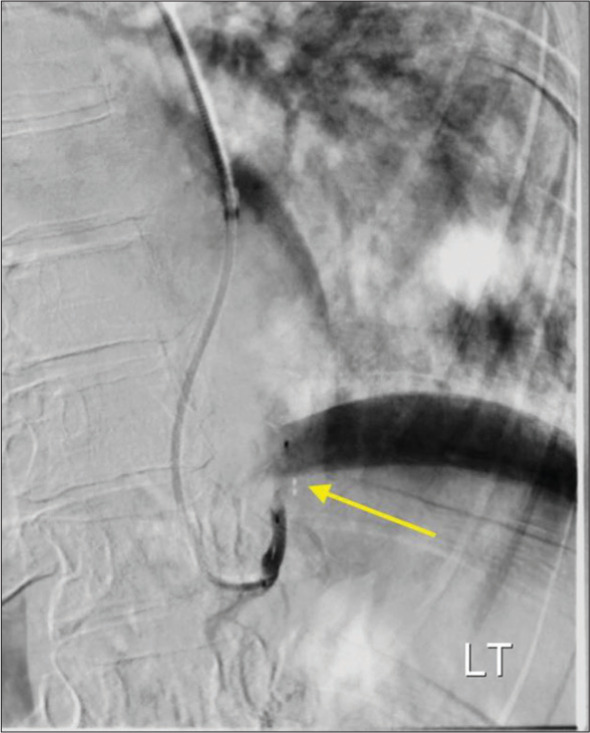

Pulmonary sequestration is a malformation of lung tissue such that a zone of pulmonary parenchyma exists in isolation from the bronchopulmonary tree. This condition is typically treated with surgical resection, but an increasing number of sequestrations are being treated with arterial embolization. We report interventions that were performed at two institutions on patients 53-70 years old. One patient presented with chronic cough and the two other patients presented with hemoptysis. Two of the cases were managed solely by endovascular embolization of the arteries supplying the pulmonary sequestration. In one patient, embolization was performed to debulk the sequestration, followed by surgical resection. These cases suggest transcatheter embolization may be an effective treatment in adult patients with symptomatic pulmonary sequestrations.